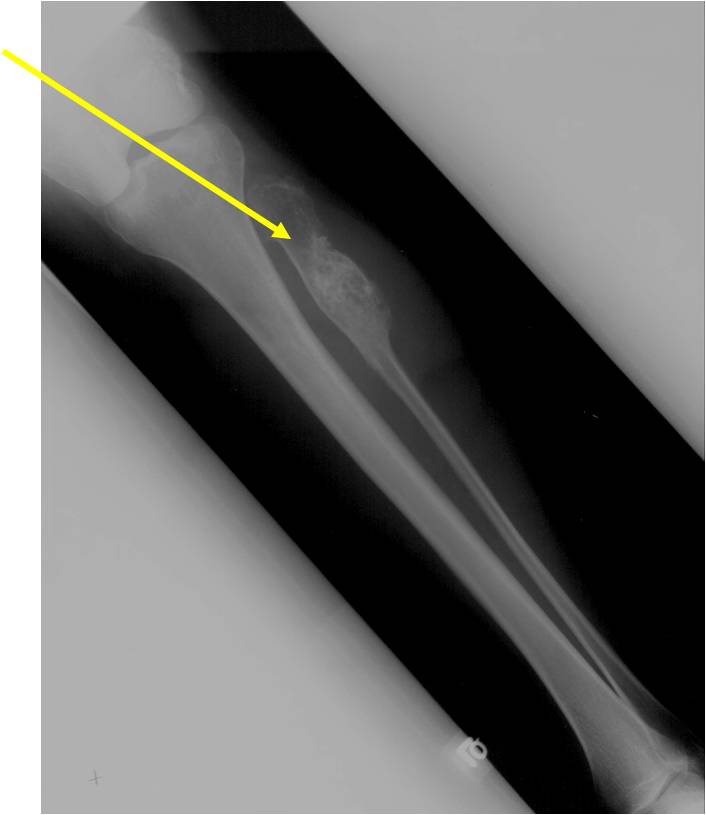

- Localized, radiolucent defect usually with punctate calcifications

- Calcifications are stippled, punctate, popcorn like calcifications and “Ring and Arc” calcifications

- Cartilage tumors grow in a lobular manner. The perimeters of the lobules undergo

- enchondral ossification that may calcify. If the entire perimeter of the lobule calcifies it appears

- radiographically as a “Ring”. If a portion of the perimeter of a lobule calcifies it forms an “Arc” on

- an X-ray.

Plain X-Ray:

- Geographic lytic lesion

- Central often metaphyseal in long bones

- Chondroid matrix with calcifications in majority of tumors